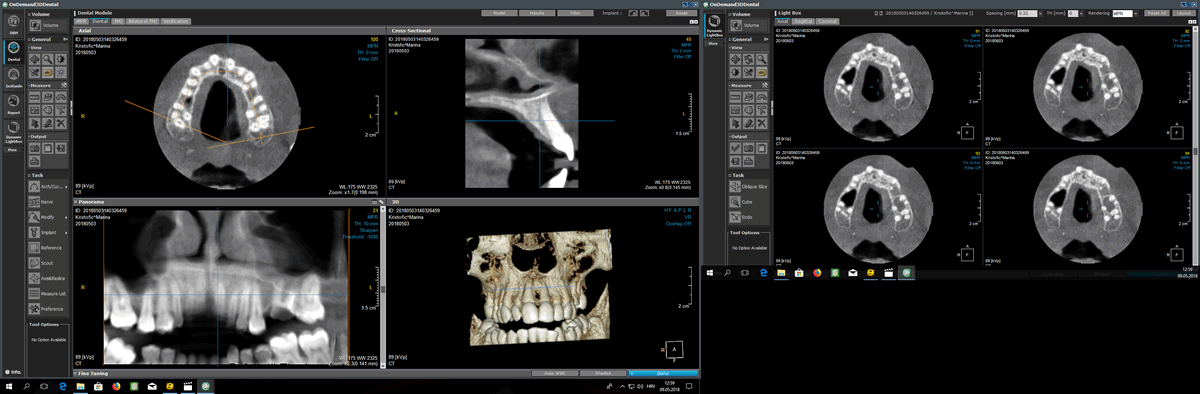

CBCT - je trodimenzionalna snimka zubi i okolne kosti koja se koristi za najdetaljniju i najprecizniju dijagnostiku. Prednost ove snimke je u tome što vidimo zube i okolnu kost u svim dimenzijama. Najčešće nam koristi prilikom implantoloških i kirurških zahvata i kod fraktura zuba.

Snimke se pregledavaju u OnDemand 3D programu.